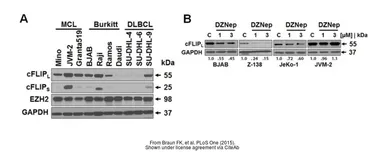

The data was published in the journal PLoS One in 2015. PMID: 25738497

The data was published in the journal PLoS One in 2015. PMID: 25738497